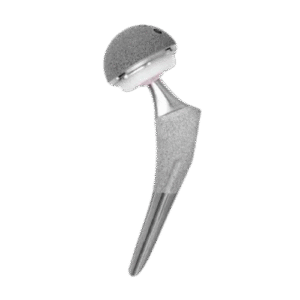

Reemplazo

articular

Artroplastia de rodilla y cadera para restaurar movilidad y aliviar dolor en articulaciones dañadas.